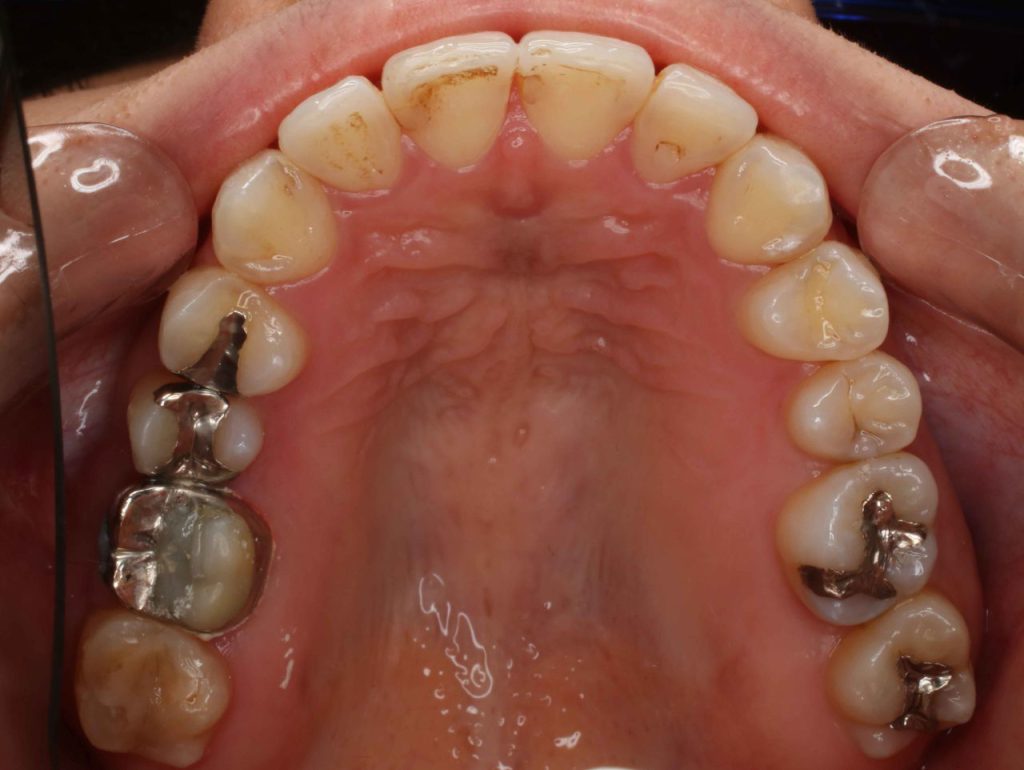

Before

今回の症例は上下全部の歯の矯正を行いました。上の前歯の先がとがって出ているハの字になているとのことで来院されました。30

このまま歯を並べてしまうスペースが無くと前方に出でしまうので上顎の臼歯を後ろに後退させることで歯を並べるスペースを作り個々の歯を後退させて綺麗なアーチに歯を並べました、最後に上下の嚙み合わせを良くする為に顎間ゴムをかけていただきました、上下の中心も揃っていてとても満足いただけました。